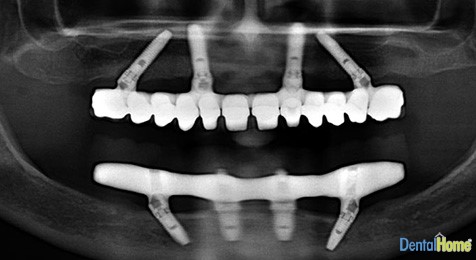

All On Four Implants, are implants used for cases where patients have had full dentures and have permanent issues with mobility, which prevents them from chewing all foods easily and mispronounce words, that is why this system has 4 completely fixed implanted dentures that allows the client to bite and speak with more confidence, improve self-esteem. Also this system improves dental and facial aesthetics while being able to enjoy food more.

This type of dental implant is perfect for use with clients who want to regain all of the lost teeth of one jaw or who do not have enough bone in some areas. Since this process is very similar to how single implants are used, it provides optimal support for a fixed dental bridge which can be made and in use in just a few days after the procedure.